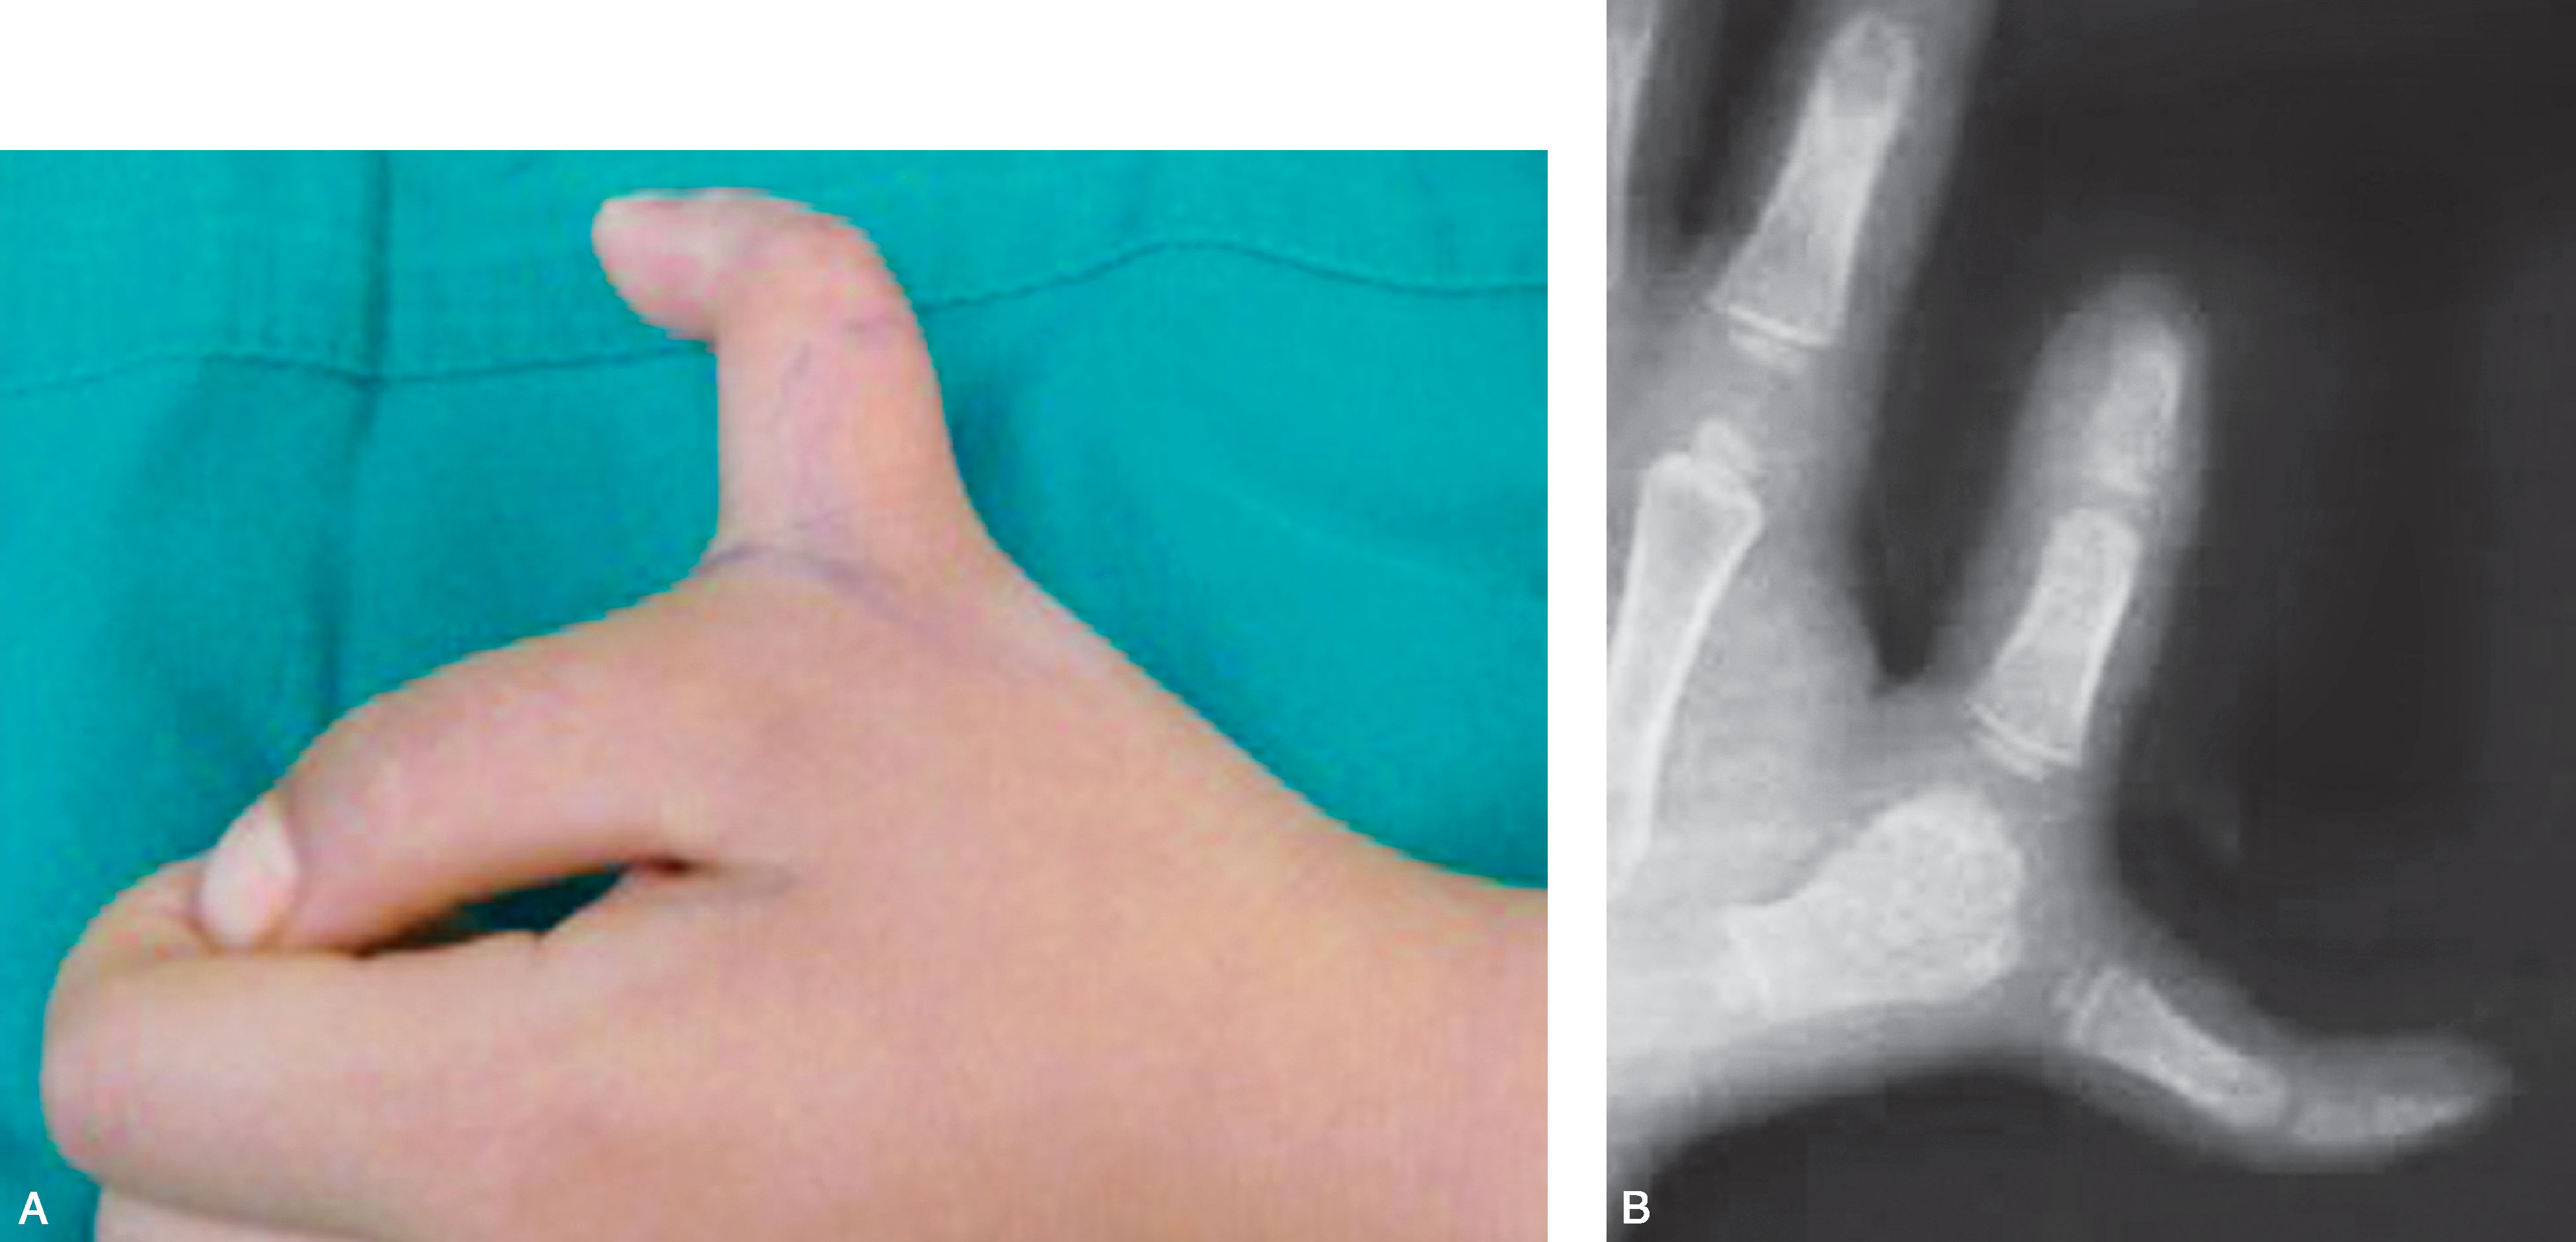

图2-1-45 Ⅵ型病例9

A.左侧多拇指,桡侧拇指畸形更为严重,尺侧拇指外形好,但掌指关节桡偏严重(提示掌指关节不稳定);B.X 线片显示桡侧拇指骨关节发育严重不良,选择切除桡侧拇指。 但尺侧拇指第一掌骨明显内收,切除桡侧拇指后,尺侧第一掌骨基底需行桡侧楔形截骨,以改善第一、二掌骨间距离,同时需复位掌指关节、紧缩掌指关节尺侧关节囊韧带,术中需保护第一腕掌关节囊韧带及拇长展肌腱止点,成人掌指关节可融合